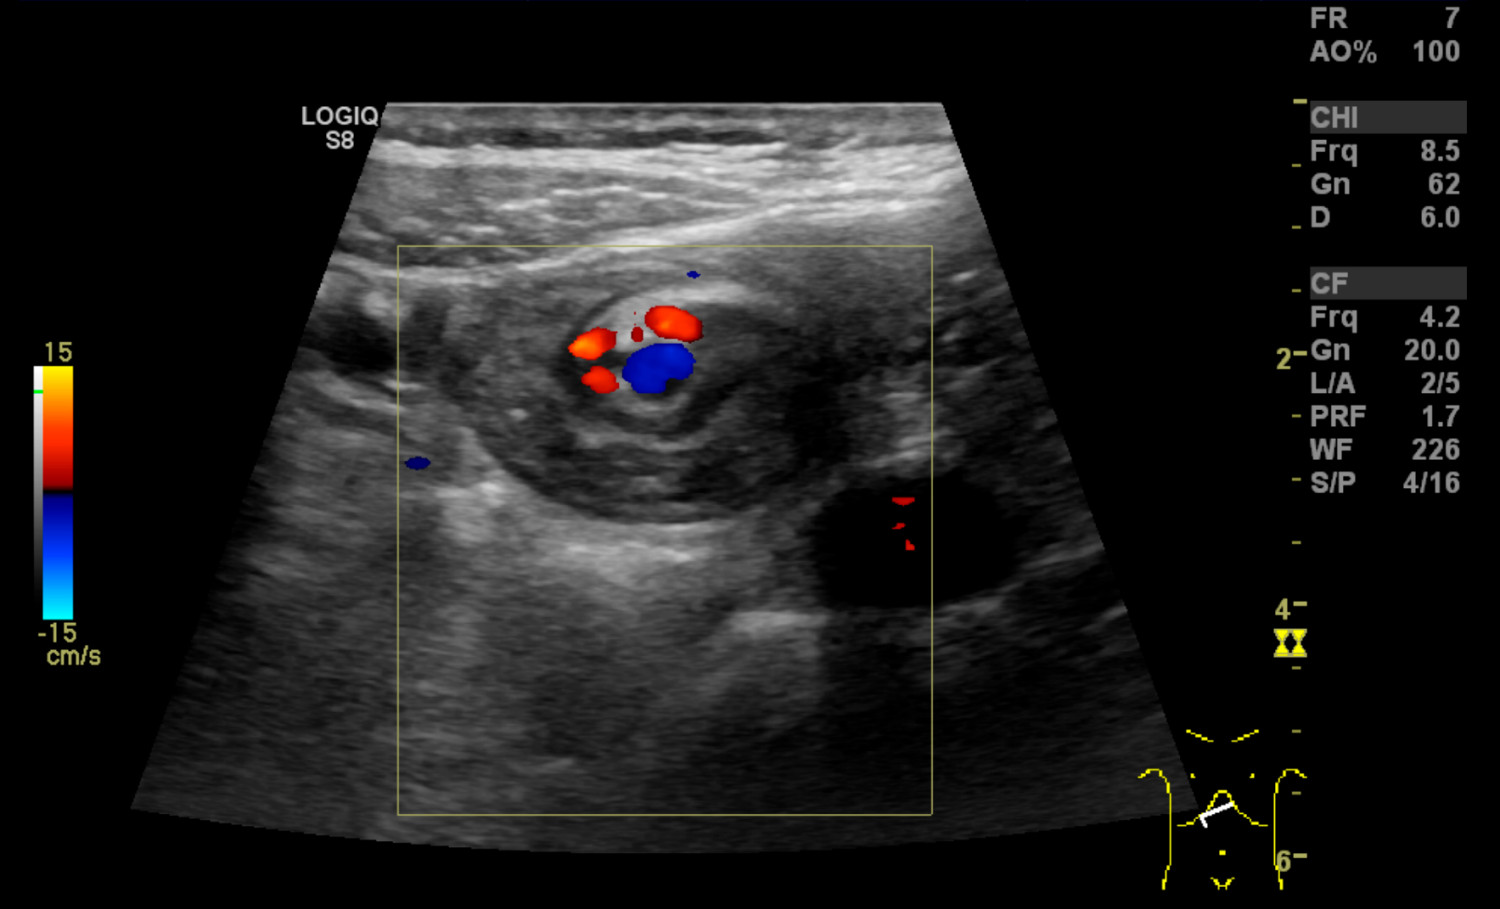

En såpass uttalt og akutt forverring passet ikke med tidligere vurderte diagnoser som abdominal migrene, gastroøsofageal refluks eller obstipasjon, og differensialdiagnostisk ble ventrikkelretensjon eller arteria mesenterica superior-syndrom vurdert. Ved innkomst startet man behandling med erytromycin (Ery-Max) mikstur 3 mg/kg for å stimulere til ventrikkeltømming, intravenøs NaCl og glukoseløsning tilsatt natrium og kalium, samt kaliummikstur 10 ml x 3 peroralt. Ultralyd abdomen ble utført av radiologisk lege i spesialisering fredag kveld, og det ble beskrevet virvellignende rotasjon (whirl sign) i epigastriet som involverte vena og arteria mesenterica superior (figur 1). Legen mistenkte intestinal malrotasjon og anbefalte i første omgang kontrollultralyd av erfaren barneradiolog på dagtid. Det ble også bemerket spiss vinkel mellom aorta og proksimale del av a. mesenterica superior, som ved mulig arteria mesenterica superior-syndrom. Det var normale funn ved røntgen oversikt abdomen.

Gjennom helgen ble jenta observert. Hun hadde bedre allmenntilstand, lite magesmerter og ingen episoder med oppkast. Elektrolyttnivået ble raskt normalisert etter påbegynt væskebehandling. Mandag formiddag ble det gjort ultralydkontroll av en erfaren barneradiolog som bekreftet funn av virvellignende rotasjon (figur 1 og 2) og som mistenkte ledsagende volvulus (tarmslyng som følge av at et tarmsegment vris rundt sin egen akse). Diagnosen ble bekreftet med røntgen øsofagus, ventrikkel og duodenum som viste kontrastpassasje til proksimale tynntarm, men ikke videre (figur 3). Overgangen mellom duodenum og tynntarm lå like til venstre for midtlinjen, kaudalt for nivå med bulbus duodeni, noe som indikerte malrotasjon med volvulus. Man hadde omsider funnet forklaringen på pasientens langvarige plager (figur 4).

Ved ultralydundersøkelse ligger normalt v. mesenterica superior til høyre for a. mesenterica superior. Hvis venen ligger til venstre eller foran arterien, gir det sterk mistanke om malrotasjon. Sensitivitet er angitt til 67–100 % og spesifisitet til 83–92 % (7). Ved unormalt leie påvist på ultralyd bør man gå videre med røntgen av øsofagus, ventrikkel og duodenum. Hos vår pasient så man på ultralyd det såkalte «whirl sign», som er regnet som 100 % spesifikt for midttarmsvolvulus (7): Duodenum, proksimale del av tynntarm og v. mesenterica superior snurrer rundt a. mesenterica superior. Bakenforliggende årsak er malrotasjon og et kort mesenterium. Midttarmsvolvulus gir en duodenal, altså en helt proksimal obstruksjon, og røntgen oversikt abdomen kan således vise helt normale funn, mens barnet likevel har en akutt, operasjonstrengende tilstand.

Ultralyd med doppler, der man kan påvise den virvellignende rotasjonen, er i trenede hender svært nyttig i diagnostikken (3) og er ofte den første bildeundersøkelsen barnet får gjort. Røntgen av øsofagus, ventrikkel og duodenum er gullstandard for diagnostikk av malrotasjon og bør alltid utføres som øyeblikkelig hjelp ved mistanke om malrotasjon – selv ved negativ ultralyd (6, 7). Til tross for at man i løpet av radiologispesialiseringen skal ha opplæring i ultralydundersøkelser på barn, kan man ikke forvente at alle kjenner til ultralydfunn ved uventet volvulus. De færreste som ikke jobber med barn, vil noen gang se det. Man bør imidlertid, både som kliniker og radiolog, være spesielt oppmerksom på babyer/barn med gallefarget oppkast. Da må malrotasjon og volvulus alltid mistenkes. Det kan være subtile abdominale symptomer initialt, og det er som regel først sent i forløpet at barnet utvikler blodig avføring og peritonitt (6). Det kan da allerede foreligge irreversibel iskemisk skade av midttarmen. Ved rask, presis diagnostikk og påfølgende kirurgi ved påvist malrotasjon kan en potensielt livstruende tilstand få et vellykket utfall.